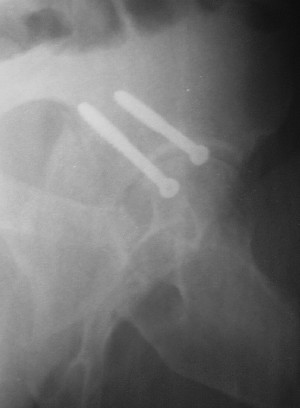

Уважаемые коллеги. Больной был оперирован в одну сессию 25 августа. Сначала на голень наложен спице-стержнвой аппарат. Затем выполнен остеосинтез вертлужной впадины Y-образным доступом. Пришлось дополнительно отсекать вертел. Шейка синтезирована спонгиозными винтами и спицами, вертел - спицами и стягивающей петлей. После операции находился на вытяжении 3 нед. Раны зажили первичным натяжением. Сейчас уже дома. Будет и дальше без нагрузки на левую ногу. Будем наблюдать в динамике. Ждем комментарии.

Перелом шейки был многооскольчатйй очень медиальный, по сути шейку и вертел расколотило об подвздошную кость с кучей мелких фрагментов, вертел был полностьб вовлечен в перелом, головка заподлицо скрывалась в расширенной вертлужной впадине. Качество кости приличное. Остатки дуги Адамса с предварительно проведенными винтами я вколотил в головку и компрессировал винтами - оказалось прочно, но образовался дефект верхнего отдела шейки, который был заплнен фрагментами фиксироваными трансфрактурными спицами - отсюда пучек.

Вертел во время доступа пришлось еще рубить, т.к.

переломы распространялись чересчур дистально.

Отсюда еще пучек спиц.